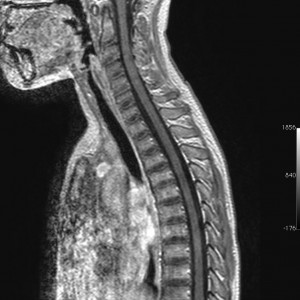

手術後のMRI

手術後にガドリニウム増強MRIで脳脊髄播種がないかどうかの確認をしました。腫瘍は全摘出できていて,複視や視野障害などもなく無症状です。